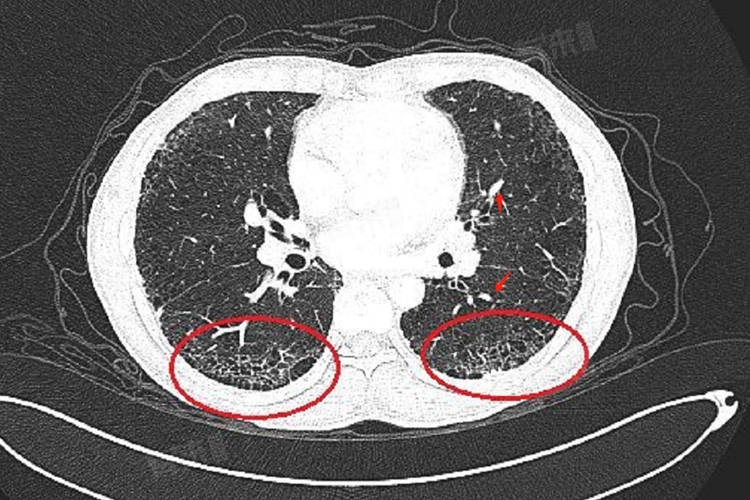

肺部出现少许条索影是否要紧要依据多种因素来判断,不同的成因、伴随症状等都会影响其严重程度,有的可能只是良性的过往痕迹,如陈旧性病变、慢性炎症导致等,无需太过担忧,而有的则可能预示着潜在疾病,需要进一步关注。

4、肺间质病变表现:若少许条索影是肺间质病变的早期表现,就要引起重视了,相对比较要紧。虽然目前条索影数量少,但肺间质病变有可能会逐渐进展,影响肺部的气体交换功能,导致呼吸困难等症状出现,需要进一步完善相关检查,如肺功能检测等,明确诊断后按医生制定的方案积极治疗,延缓病情发展。

当发现肺部有少许条索影时,不要过于惊慌,应向医生详细了解可能的原因。严格按照医生建议定期复查胸部影像学,对比条索影变化。保持健康生活方式,如适当锻炼、规律作息、均衡饮食,利于肺部健康,若出现不适症状及时就医。